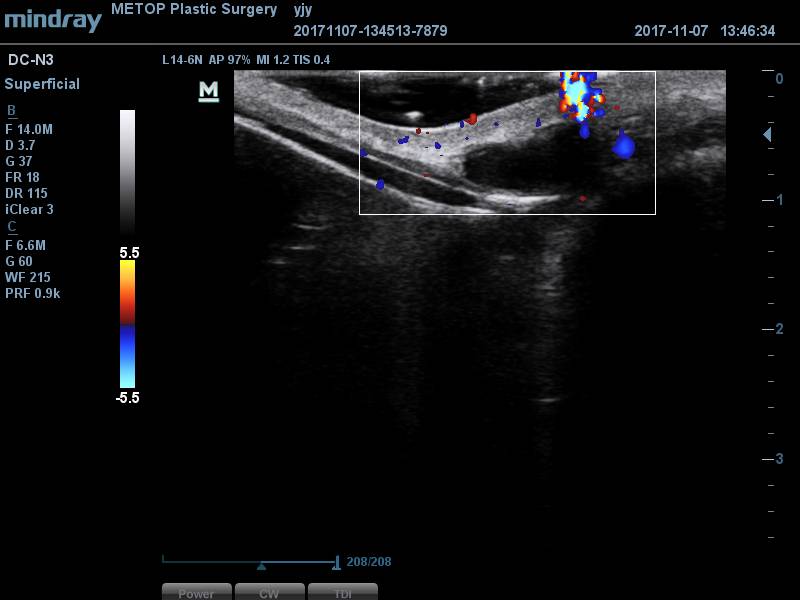

[얼굴이물질제거] 코필러이물질제거

코필러이물질제거